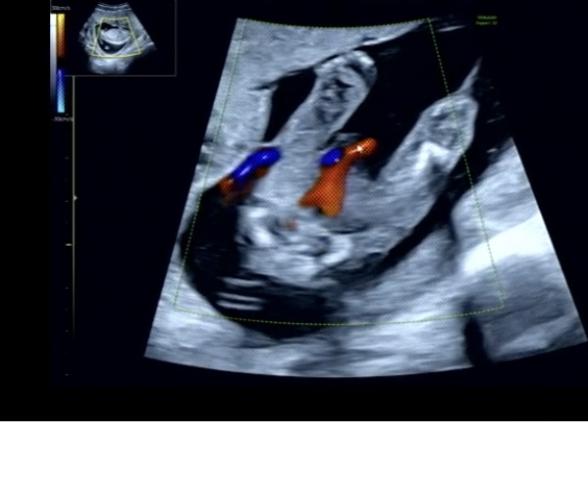

17w5d、性別は?

13wに胎児ドックを行った時には男の子かもと言われていましたが

17wでの検診の時には女の子だと言われました!

次の検診まで確定ではないとは言われていますが、、

赤ちゃんの性別についてですね。

拝見していて、はっきりと男の子のシンボルはわからず、女の子のサインとされるお股のあたりに見られるようになる葉っぱのマーク、サインが、添付をしてくださったものからは分かりませんでした。